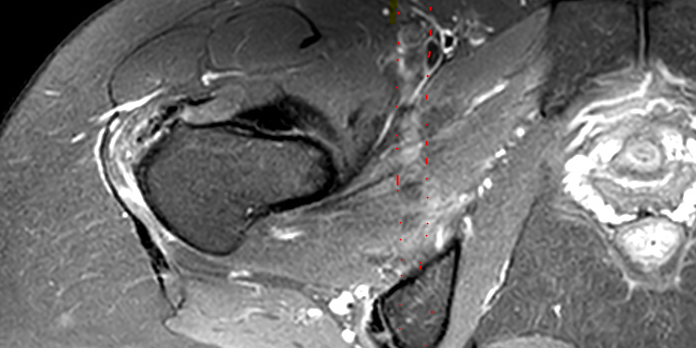

L’immagine DI Risonanza Magnetica è un immagine 2D, definita da 2 dimensioni nello spazio, X e Y. Durante l’acquisizione del segnale queste due dimensioni vengono associate alla decodifica del segnale della fase e a quello della frequenza.

L’operatore può scegliere quale delle due decodifiche assegnare all’asse X e di conseguenza quale sarà assegnata all’asse Y.

Le possibilità rispetto a strati disposti secondo dei i 3 piani dello spazio:

-in assiale le scelte possibili sono AP e RL

-in coronale le scelte possibili sono SI e RL

-in sagittale le scelte possibili sono AP e SI